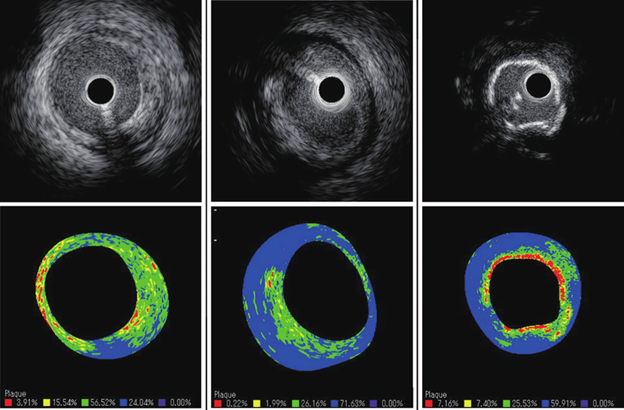

- Ultrassom intravascular

Método de imagem intravascular que utilizada ondas de ultrassom para o detalhamento do interior das artérias, usado para o diagnóstico e tratamento de doenças das artérias coronárias. O método de histologia virtual permite ainda correlacionar as imagens com os tipos de tecidos envolvidos na doença, como a presença de cálcio e gordura.

Acima, imagens do interior de uma artéria coronárias e, abaixo, a representação em cores dos tipos de tecidos.